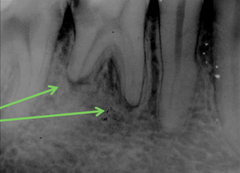

root absess

Front

collection of puss at apex of root. appears as radiolucent circle

Back